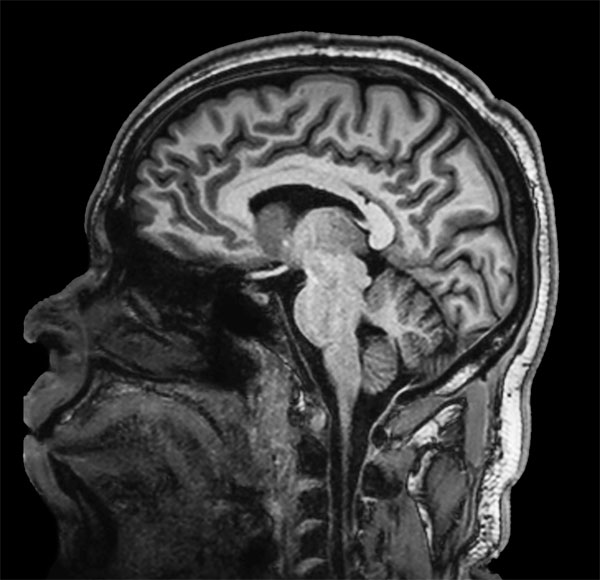

dS SENSE in Brain Imaging

Used Solution

• Clinical Application